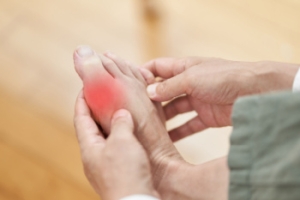

Gout can easily be identified by redness and inflammation of the big toe and the surrounding areas of the foot. Other symptoms include extreme fatigue, joint pain, and running high fevers. Sometimes corticosteroid drugs can be prescribed to treat gout, but the best way to combat this disease is to get more exercise and eat a better diet.

Gout is a form of arthritis that commonly affects the feet, especially the big toe joint, and develops when uric acid crystals build up around a joint. The earliest stage of gout, called asymptomatic hyperuricemia, involves crystal deposits without pain. The second stage, acute intermittent gout, is when sudden attacks occur, often at night or early in the morning. These episodes cause severe pain, redness, swelling, and warmth in the affected toe, ankle, or foot joint. It sometimes makes it difficult to walk or even touch the area. If gout is not properly managed, it can progress to chronic tophaceous gout, where hard deposits, known as tophi, form under the skin or within joints. This advanced stage can cause ongoing pain, deformity, stiffness, and limited mobility in the toes, feet, or ankles. If you are experiencing foot pain related to gout, it is suggested that you make an appointment with a podiatrist for a diagnosis and ongoing help managing this painful condition.

Gout is a type of arthritis caused by a buildup of uric acid in the bloodstream. It often develops in the foot, especially the big toe area, although it can manifest in other parts of the body as well. Gout can make walking and standing very painful and is especially common in diabetics and the obese.